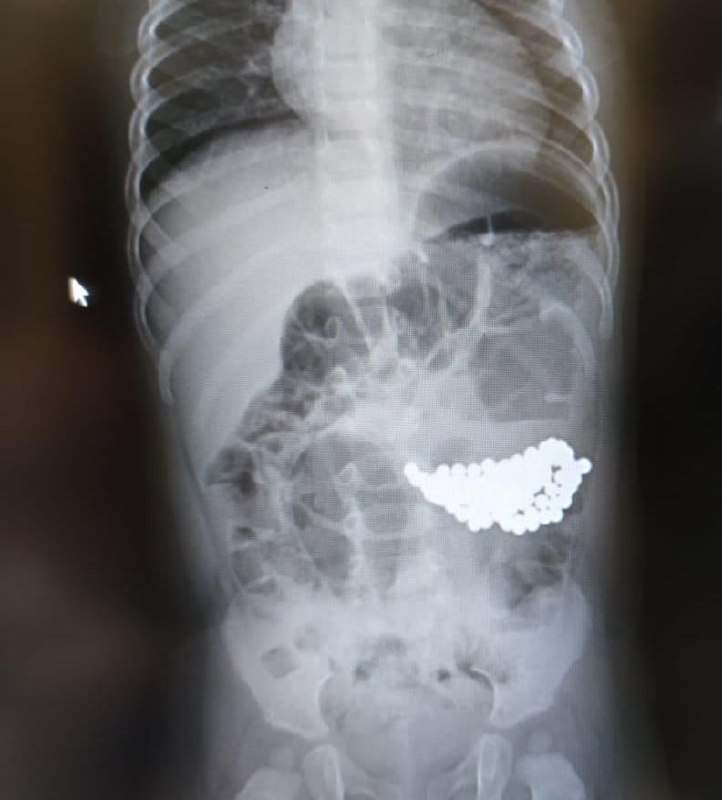

Годовалого мальчика экстренно доставили в Детскую больницу №9 им. Г.Н. Сперанского Департамента здравоохранения Москвы с большим скоплением инородных тел в желудке – малыш проглотил больше сотни шариков магнитного конструктора.

Мальчик играл под присмотром своей старшей сестры. И только когда мама начала собирать игрушки, оказалось, что не хватает целой половины набора магнитного конструктора. Родители немедленно вызвали скорую помощь, и фельдшеры приняли решение обследовать обоих детей в стационаре. После проведения рентгеновского исследования девочку сразу отпустили домой – в результатах не было ничего необычного. А ее младшего брата экстренно доставили в операционную – снимок показал, что в желудке у мальчика собрался огромный ком из магнитных шариков.

– Специальными инструментами мы извлекли из желудка пациента аж 117 мелких инородных предметов! – рассказывает заведующий отделением гнойной хирургии №2 Нодари Зурбаев. – К счастью, магнитные шарики, притянувшись друг к другу, не успели нарушить функцию желудка. После операции малышу назначили антибактериальную, инфузионную терапию. Сейчас ребенок в полном порядке, его уже готовят к выписке.

Специалисты Детской больницы №9 им. Г.Н. Сперанского настоятельно рекомендуют не допускать игр маленьких детей с мелкими предметами без постоянного присмотра взрослых, а также всегда обращать внимание на возрастные рекомендации и ограничения игрушек.